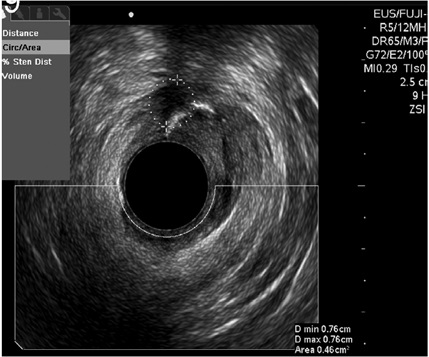

Por otro lado, en el grupo masculino con estudio por incontinencia, el diagnóstico en todos fue cambios por atrofia del aparato esfinteriano, que pudo verse en cualquiera de las localizaciones del canal anal y que se evidenció como engrosamiento de los músculos en general y cambios difusos de la ecogenicidad de los mismos, sin posibilidad de determinar el borde que los delimita. Se encontró fístula perianal en 16 pacientes (11,8%); la principal forma de presentación de las fístulas fue transesfintérica (37,5%), seguida por las interesfintéricas y anovaginales (figuras 3 y 4). Doce pacientes presentaron absceso perianal (8,8%); de estos, el 83% correspondió a abscesos submucosos o isquiorrectales (figura 5).

Los demás diagnósticos finales se presentan en la tabla 4. Es de resaltar que se pudo determinar en el grupo diagnosticado como neoplasia benigna de recto, la posibilidad de resección endoscópica en lesiones que tenían planeadas cirugías más invasivas (figura 6 y 7), así como la posibilidad de determinar la recuperación del aparato esfinteriano en 3 pacientes en seguimiento por cáncer de canal anal después de manejo por parte de oncología. En 2 pacientes de los diagnosticados con neoplasia maligna de recto se identificó lesión menor a T2 y N0 según las clasificación de TNM (figura 8), considerándose lesiones tempranas; en el otro 88,8% se encontraron lesiones avanzadas (figura 9 y 10). También se anota que, dentro de la categoría otros, están con orden de frecuencia de mayor a menor endometriosis o endometrioma, enterocele, fisura anal, várices rectales y un caso de cáncer de colon sigmoides.